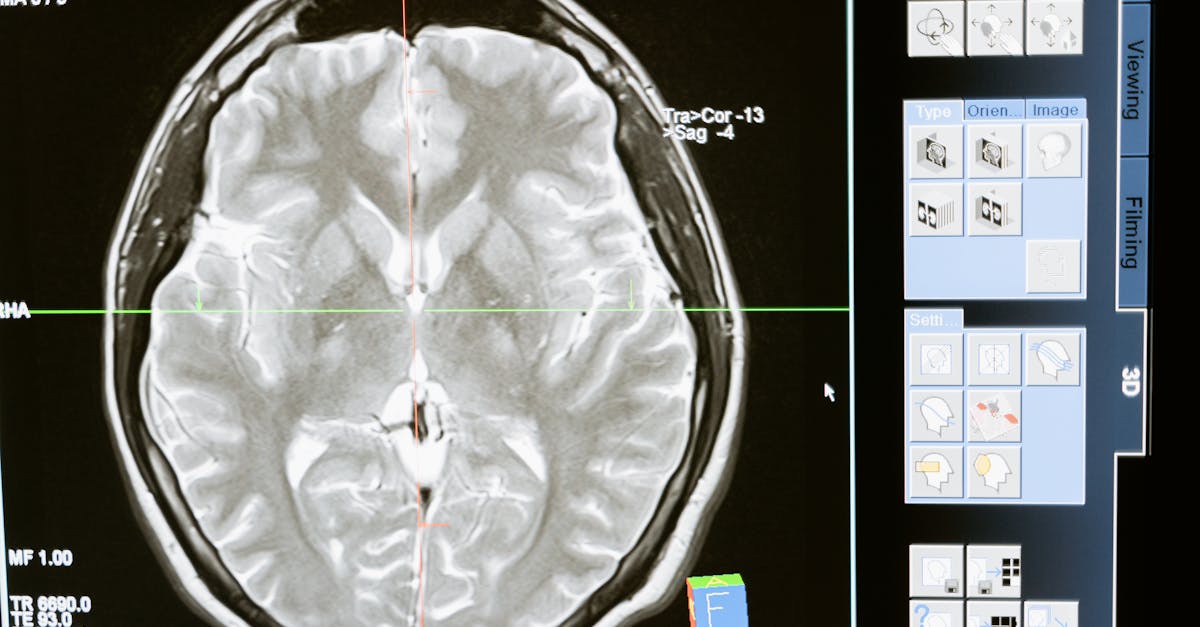

Typically, the dementia testing process begins with a thorough medical history and mental status examination conducted by a healthcare professional. This can include a variety of cognitive tests designed to assess memory, attention, problem-solving abilities, and language skills. Additional tests, such as blood tests and brain imaging, may be ordered to rule out other conditions affecting cognitive function. It’s essential to bring along a family member or close friend who can provide insights into observed changes in behavior and cognition, as they can play an important role in the diagnostic process.